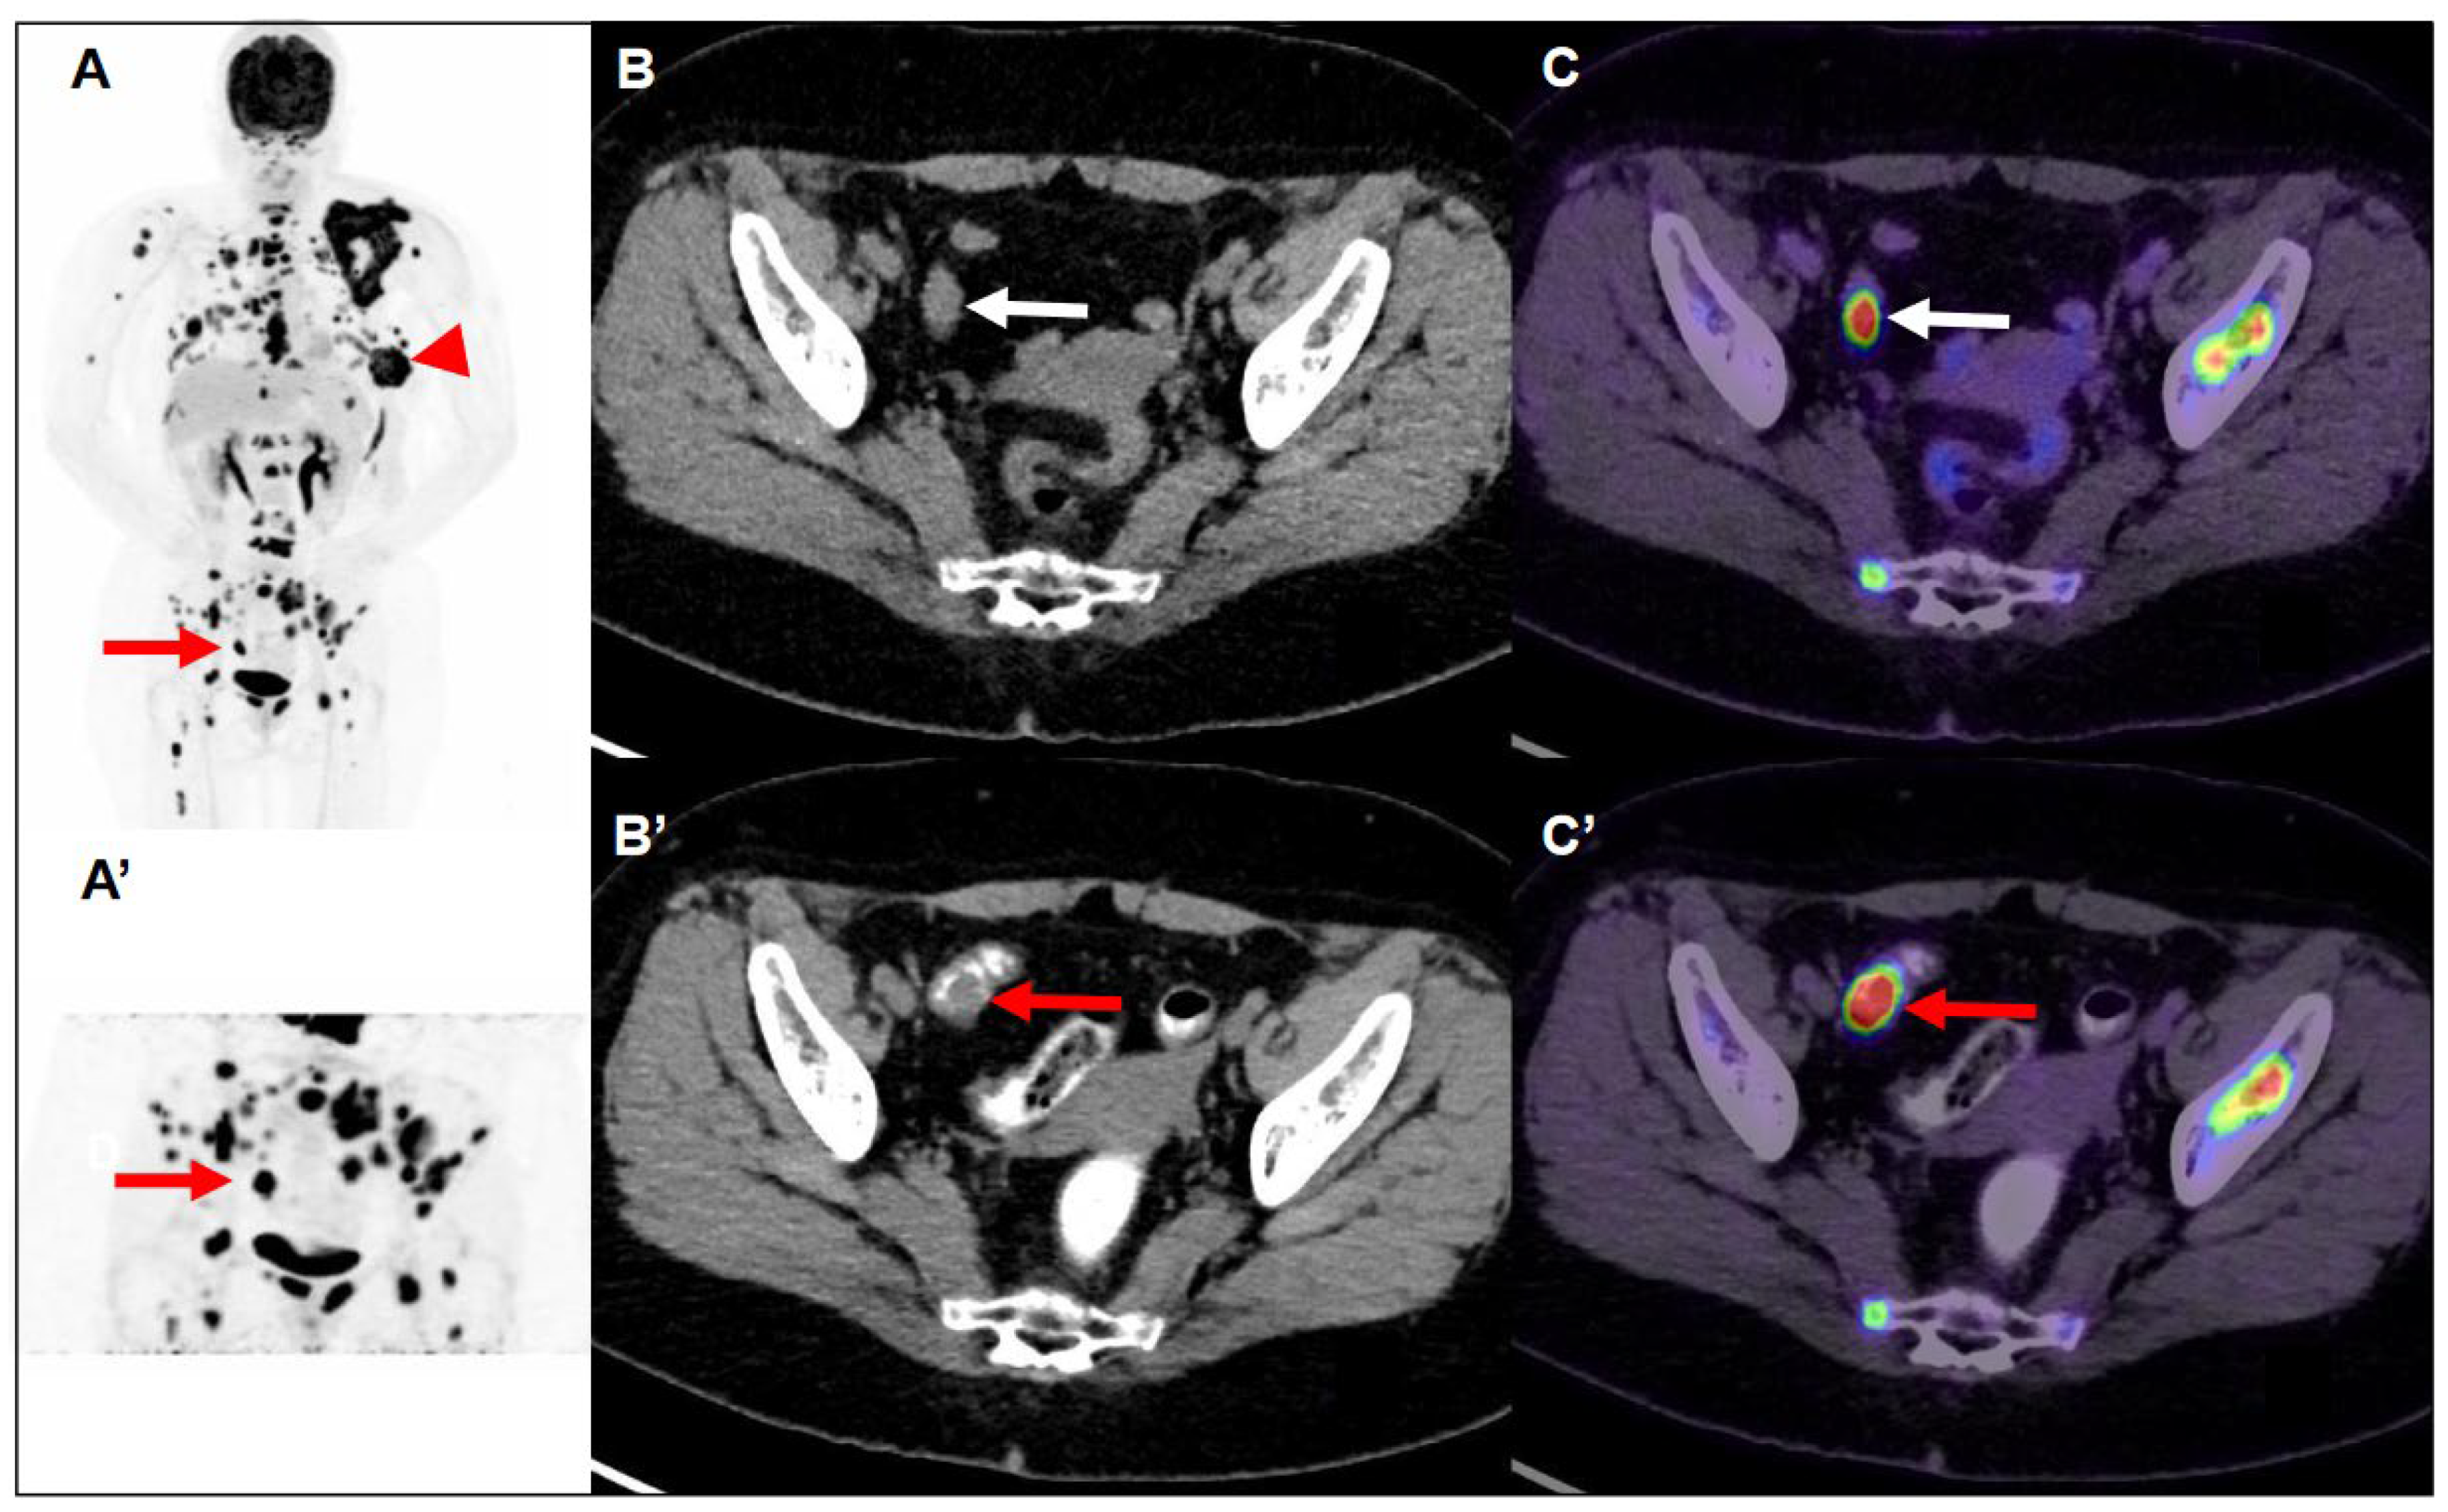

Figure 1. Maximum-intensity-projection image of FDG PET/CT (A) demonstrated multiple nodules with intense FDG uptake in the left breast (Largest: central necrosis, 5.9 cm, maxSUV:23.3) extending to the skin (arrowhead). There are lymph nodes with mild increased to intense FDG uptake in the left axilla level I/II and lower paratracheal and right hilar. There is focal intense FDG uptake in the skull, facial bone, C/T/L/S-spine, bilateral scapulae, bilateral clavicle, bilateral humerus, bilateral rib cages, sternum, bilateral pelvic, and bilateral femoral bone. Multiple nodules with intense FDG uptake in the bilateral lungs. So, it is advanced left breast cancer with multiple nodal, pulmonary, and bony metastases. In addition, transaxial CT (B) and fused FDG PET/CT images (C) demonstrated focal intense FDG uptake (maxSUV 60.9) in the sigmoid colon (white arrow), but the hypermetabolic focus could not be clearly delineated on the CT images. So, 40 min later, maximum-intensity-projection (A’), transaxial CT (B’), and fused PET/CT images (C’) of delayed FDG PET/CT scan after per-rectal administration of laxative-augmented contrast medium revealed a filling defect with persistent intense FDG uptake (maxSUV 50.8) in the sigmoid colon (red arrow), suggesting a hypermetabolic space-occupying lesion in bowel lumen. The FDG PET/CT images were acquired using a Siemens Biograph mCT (PET/CT) scanner (Siemens Medical Solutions) with an average spatial resolution of 4.4 mm at 1 cm and of 5.0 mm at 10 cm from the transverse field of view (FOV) and a maximum sensitivity of 8.1 kcps/MBq at the center of the FOV. After IV administration of 185 MBq (5 mCi) of FDG and a standard uptake period of 60 min, emission images were acquired for 3 min per bed position. Images were reconstructed using proprietary Siemens HD PET software (XP) with the iterative TrueX + TOF OSEM method. In addition, the images were analyzed semi-quantitatively using the standard uptake value (SUV) in the patient.

A 60-year-old woman had a family history of breast cancer. Her sister was diagnosed with breast cancer younger than age 40. Her mother was diagnosed with breast cancer over the age of 70. She presented with a left breast mass with intermittent tenderness for six months. Left shoulder pain and mild weakness in left arm elevation for several months were also complained. On physical examination, a tumor was palpated in the left breast at 5 o’clock position. Sonography revealed an irregular-shaped 4.4 × 3.1 cm tumor in her left breast with heterogeneous internal echo, hypervascularity around the tumor, and posterior acoustic shadowing. The tumor was given a Breast Imaging-Reporting and Data System score of 4a (BIRADs 4a). Core needle biopsy revealed an invasive ductal carcinoma with estrogen receptor (ER) negative, progesterone receptor (PR) negative, and human epidermal growth factor receptor (HER2) 1+ score. The proliferative index (ki67) of tumor cells is 90%. On laboratory investigations, the patient’s serum carcinoembryonic antigen (CEA) and cancer antigen 15-3 (CA15-3) were in the normal ranges. As a part of the pre-operative cancer staging, an FDG PET/CT scan (Simens, Biograph mCT, Munich, Germany) was performed after 8 h of fasting. FDG PET/CT scan showed a central necrotic tumor measuring 5.9 cm with a maximum standard uptake value (maxSUV) of 23.3 in the left breast, extending to the skin, which corresponded to the left breast tumor seen on sonography. Several smaller left breast nodules with various degrees of FDG uptake are found. Furthermore, bilateral lung nodules, bony lesions in axial and proximal appendicular skeletons (skull, facial bones, cervical spine, thoracic spine, lumbar spine, sacrum, bilateral scapulae, bilateral clavicles, bilateral humeri, bilateral ribs, sternum, bilateral pelvis, and bilateral femora), and multiple lymph nodes in the left axilla, lower paratracheal space, and right lung hilum with mild to intense FDG uptake are also noted. Advanced left breast cancer with multiple regional nodal, distant nodal, pulmonary, and bony metastases was depicted and classified as clinical T4bN2M1, stage IV, according to the American Joint Committee on Cancer (AJCC), 8th edition. Aside from the aforementioned findings, focal intense FDG uptake in the sigmoid colon was found (Figure 1). A delayed scan with per-rectal administration of laxative-augmented contrast medium (Fleet enema, Lynchburg; Xenetix, Gurbet) revealed a 1.5 cm nodular filling defect with a maxSUV of 50.8 in the sigmoid colon. Subsequent colonoscopy was performed smoothly with good bowel preparation and reached the cecum. A 1.5 cm polyp in the sigmoid colon was disclosed and removed with piecemeal endoscopic mucosal resection (Figure 2). Histopathology report of the specimen revealed colonic mucosa with the proliferation of atypical glandular cells arranged in irregular glands infiltrating in the desmoplastic stroma, suggesting an adenocarcinoma.

The use of a laxative-augmented contrast medium before a delayed FDG PET/CT scan leads to a reduction in the number of false-positive findings and increases the accuracy in the detection of colorectal cancer [16]. Delayed FDG PET/CT performed after administration of a laxative-augmented contrast medium might be useful for identifying patients needing additional diagnostic procedures or avoiding unnecessary colonoscopic evaluation. The rectosigmoid protocol consists of an initial phosphosoda enema (Fleet; C.B. Fleet, Lynchburg, Va). Following the evacuation, 500 mL of diluted 3% contrast medium was instilled into the anus. In our case, we used per-rectal administration of laxative-augmented contrast medium. An FDG-avid filling defect was discovered on FDG PET/CT scan. Like the PET/CT mapping technique, a laxative-augmented contrast medium may be considered a sort of functional and anatomic fusion application because the laxative has a functional effect to facilitate bowel motility, whereas the contrast agent allows anatomic representation to illustrate the bowel structures (Figure 1C’). In the previous study, we applied this imaging protocol to help decrease the false positive rate of colorectal FDG uptake from 14.4% (1464 participants) at initial PET to 0.9% (93 participants) at delayed PET/CT. The proportion of colon adenoma to adenocarcinoma detected by FDG PET/CT scan is about 73% to 27% [17]. Our patient received a colonoscopy one week later, and a 1.5 cm polyp in the sigmoid colon was found, which was proved to be adenocarcinoma.